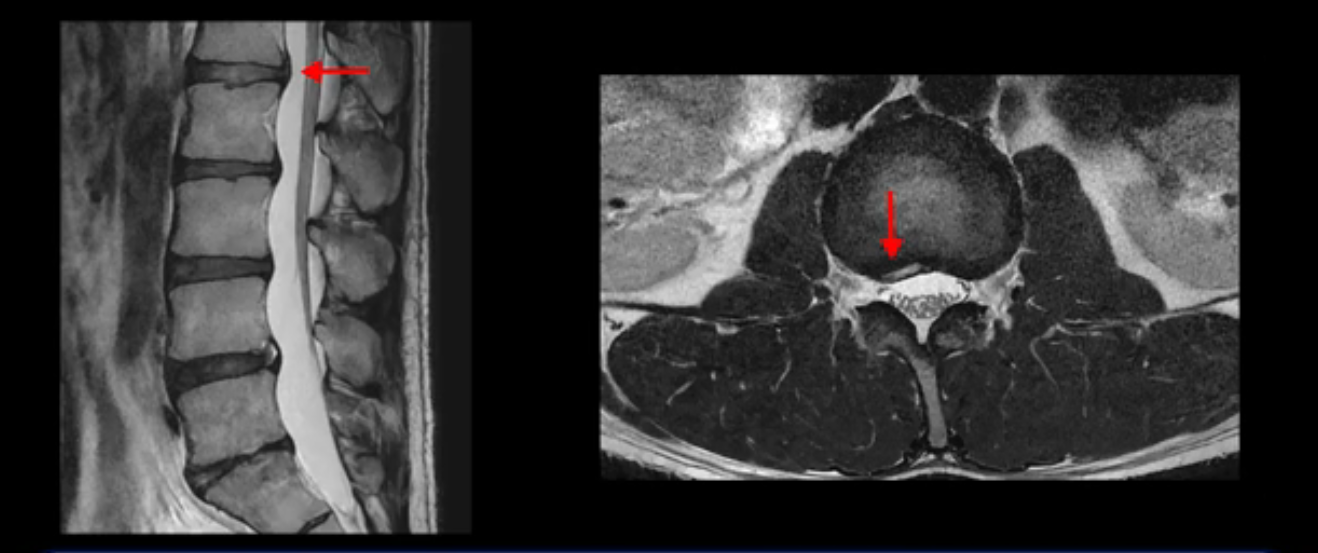

이분은 어떤 한 병원에서 디스크 내장증 얘기를 들으셨는데요. 여기 보시는 것처럼 4번 5번의 하얀 HIZ(High Intensity Zone)을 보고 디스크 내장증의 근거로 얘기하는 병원들이 있는데,

이 HIZ는 섬유륜이 찢어졌다가 이미 아문 뒤에도 얼마든지 보일 수 있는 흔적일 가능성이 있어서 재채기를 하면 아픈지, 허리를 구부릴 때 날카로운 통증이 생기는가 등의 증상으로 구별해야 하는데 MRI만 보고 HIZ가 보이면 그게 마치 통증의 원인인 것처럼 얘기하는 의사들이 있습니다. 이분 MRI를 자세히 보고 증상을 정말 자세히 들어본 의사가 있었더라면 다른 환자분들처럼 증상과 MRI가 일치하지 않는다는 얘기를 들을 수 있었을 텐데 이분은 그런 얘기는 듣지 못했습니다.